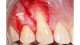

The images contained in this gallery are the property of Dr. Edward Gottesman.

Images have not been digitally altered in any way, shape, or form. These images may not be copied, downloaded or distributed without their express written permission.

Warning: Some surgical photos are intended for clinical and educational purposes and may be too graphic for some viewers.